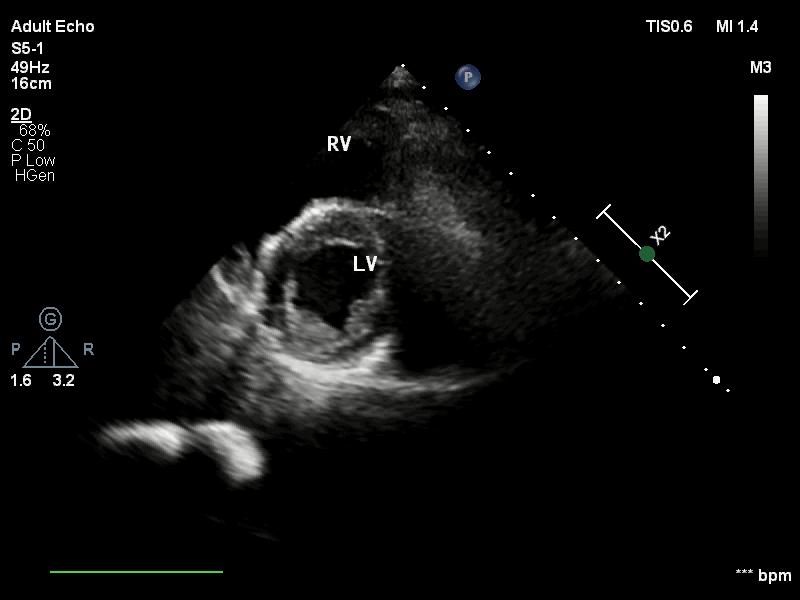

心尖区声窗常用切面2.1心尖两腔心切面

心尖两腔心切面二维超声心尖两腔心切面二维超声